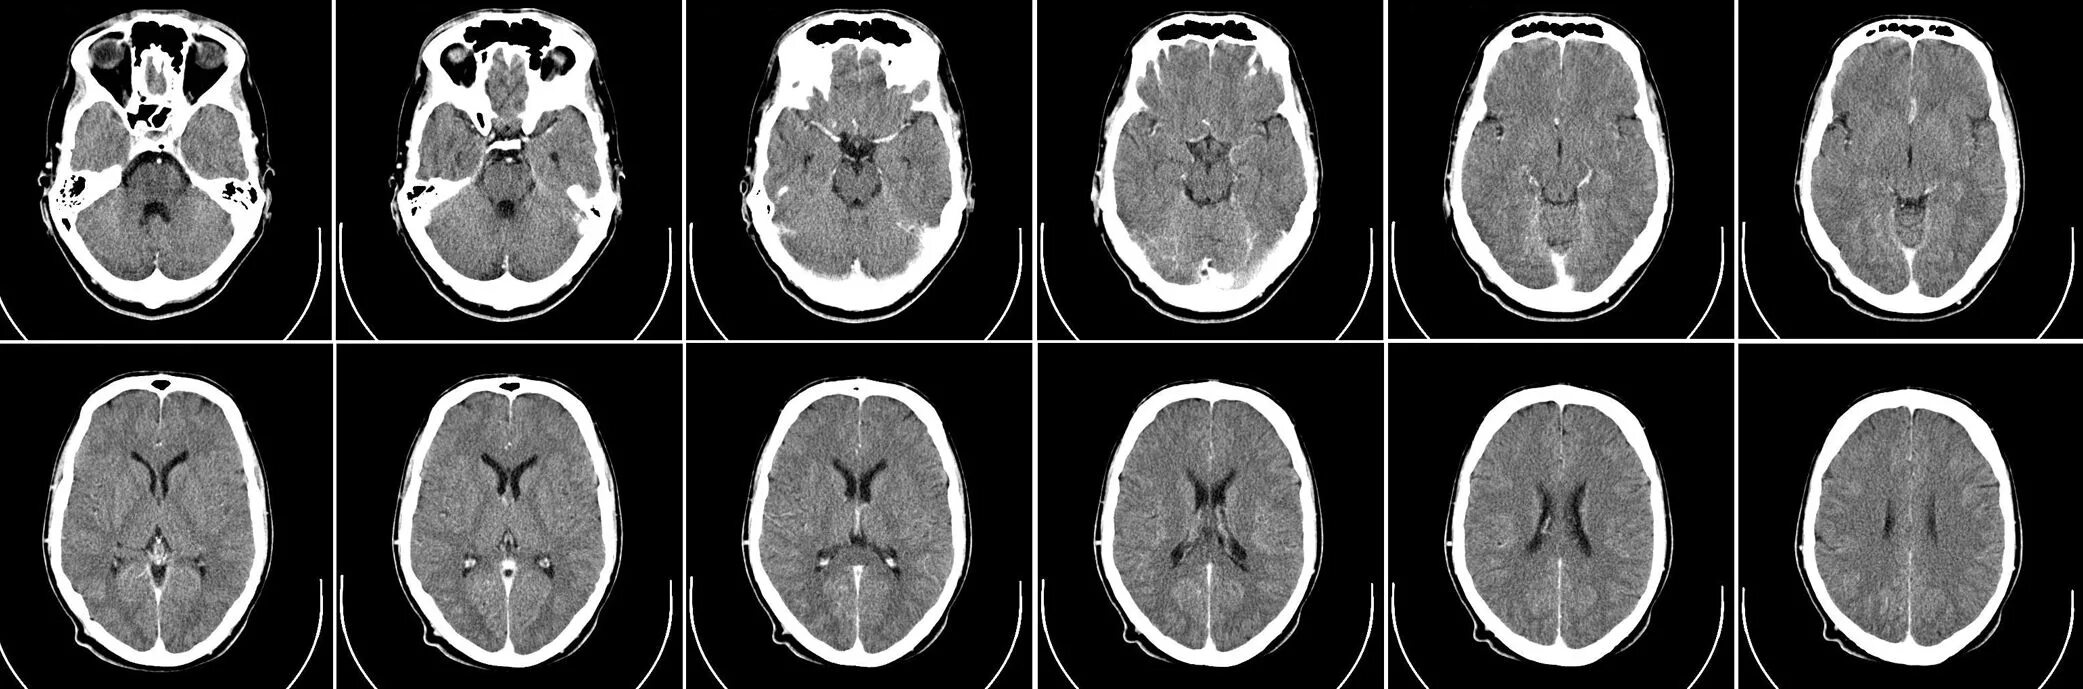

Какие виды кт